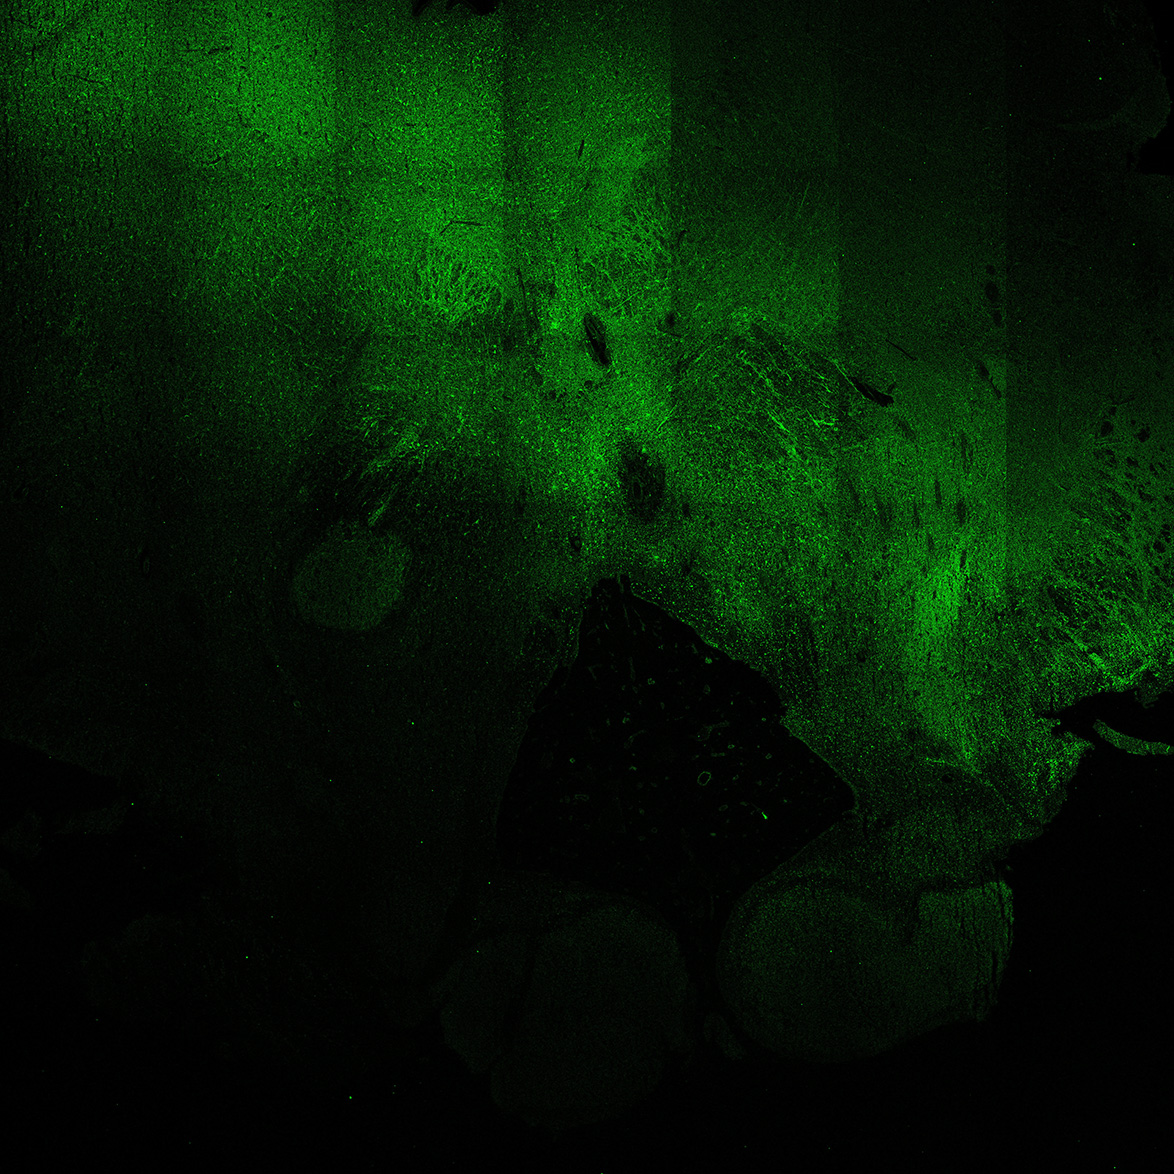

TH

7PCW human midbrain